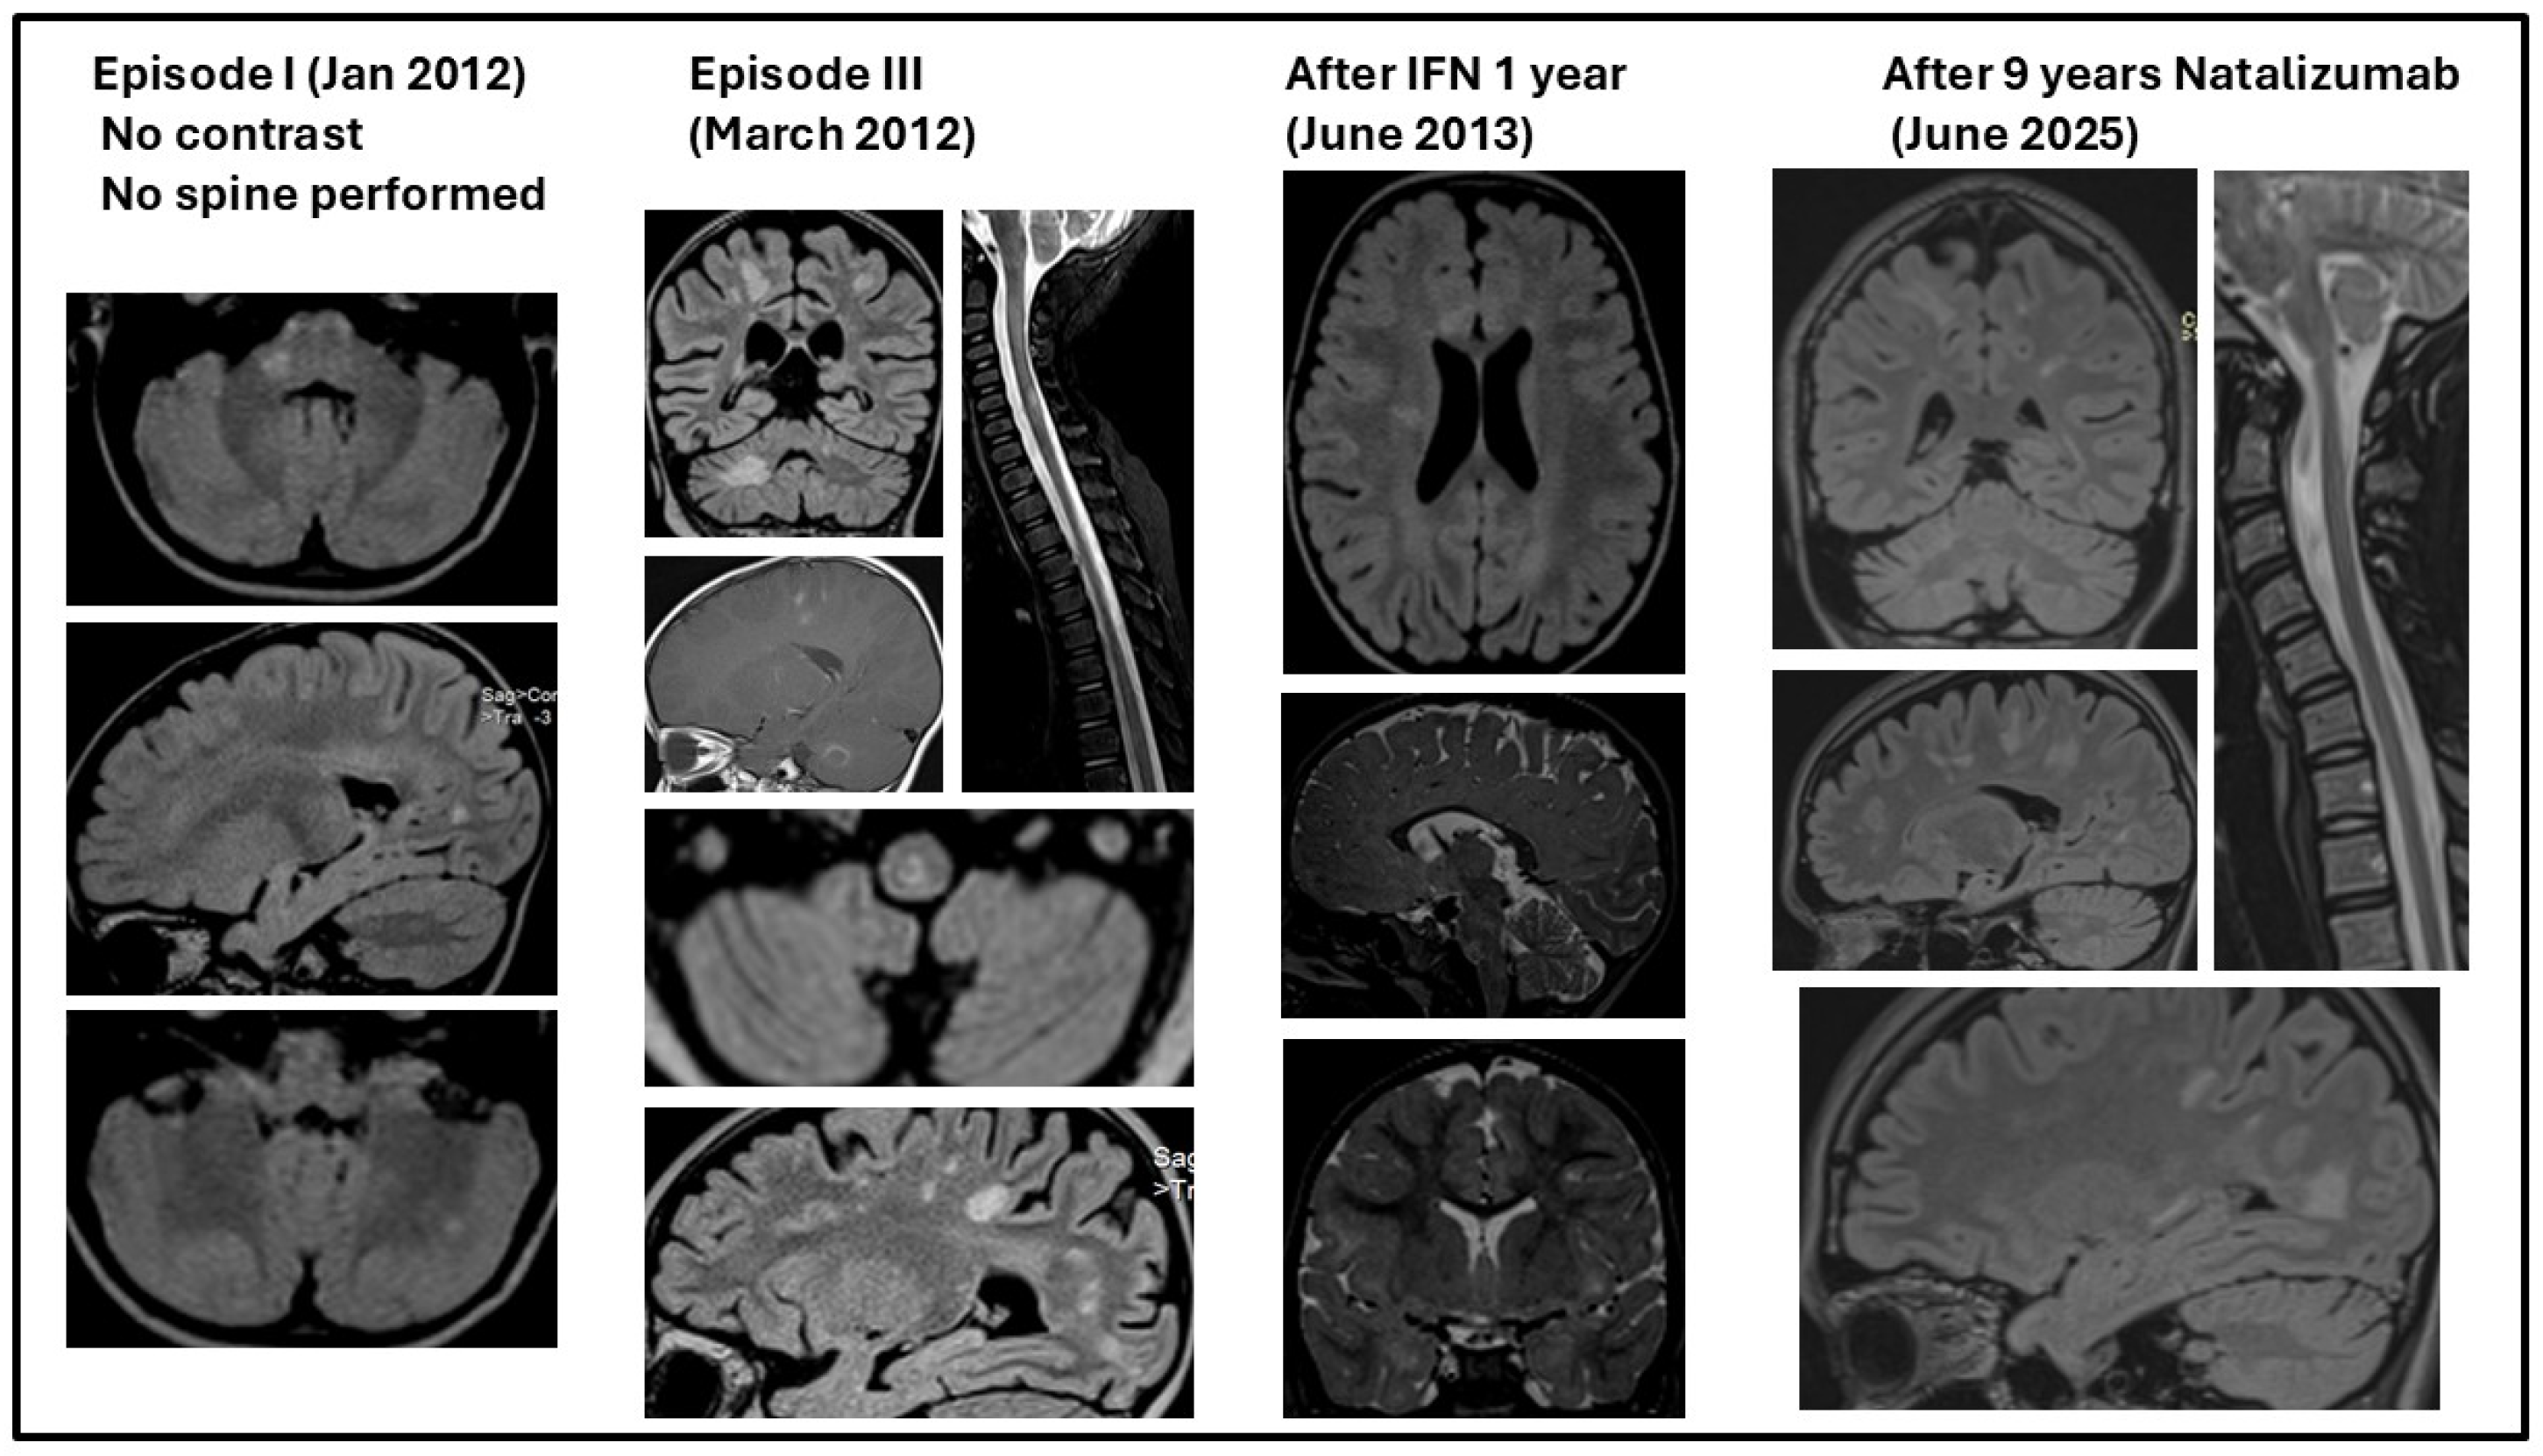

3.3.2. Evolution Under Treatment

| I | 2 y 4 m | Severe truncal ataxia Irritability | 5 w | Complete | - | 30 d | ACTH 0.5 mg/day—14 d Prednisone 0.5 mg/kg/day—7 d | - | |

| II | 2 y 6 m | Severe ataxia (R > L CS) Irritability | 5 w | Complete | - | 30 d | Dexamethasone 8 mg/day—3 d ACTH 1/3 mg/day—14 d | - | |

| III | 2 y 8 m | Severe ataxia (CS) L > R PS Irritability Saccadic speech (CS) | 3 w | Incomplete | L pyramidal Mild ataxia | 30 d | Methylprednisolone i.v. 30 mg/kg/day—6 d Tapered with Medrol IVIG 2 g/kg (in 6 d) | - | Diagnosis = RRMS |

| IV | 2 y 10 m | Severe ataxia (CS) L > R PS Irritability | 1 w | Incomplete | L pyramidal Mild ataxia | 30 d | Methylprednisolone i.v. 30 mg/kg/day—5 d Tapered with Medrol | IFN beta-1a * | |

| V | 2 y 11 m | Severe ataxia (CS) L > R PS Irritability | 1 w | Incomplete | L pyramidal Mild ataxia | 60 d | Methylprednisolone i.v. 30 mg/kg/day—5 d Tapered with Medrol | ||

| VI | 3 y 1 m | Irritability, mild ataxia | 2 d | Incomplete | Mild L pyramidal | 60 d | - | ||

| VII | 3 y 3 m | Irritability, mild ataxia | 2 d | Incomplete | Mild L pyramidal | 10 m | - | ||

| VIII | 4 y 1 m | Slight left intentional tremor (CS) Mild left hemiparesis (PS) | Not known | Incomplete | Mild L pyramidal | 13 m | Methylprednisolone i.v. 30 mg/kg/day—5 d Tapered with Medrol | IVIG 2 g/kg/administration—monthly | |

| IX | 5 y 2 m | Mild left hemiparesis | 1 w | Incomplete | Mild L pyramidal | 11 m | Methylprednisolone i.v. 30 mg/kg/day—5 d Tapered with Medrol | ||

| X | 6 y 1 m | Mild left hemiparesis | 1 w | Incomplete | Mild L pyramidal | 12 m | Methylprednisolone i.v. 30 mg/kg/day—5 d Tapered with Medrol | ||

| XI | 7 y 1 m | Mild left hemiparesis | 1 w | Incomplete | Mild L pyramidal | 9 y–present | Methylprednisolone i.v. 30 mg/kg/day—5 d Tapered with Medrol | Natalizumab 300 mg/dose every 28 d | No relapses since initiation |